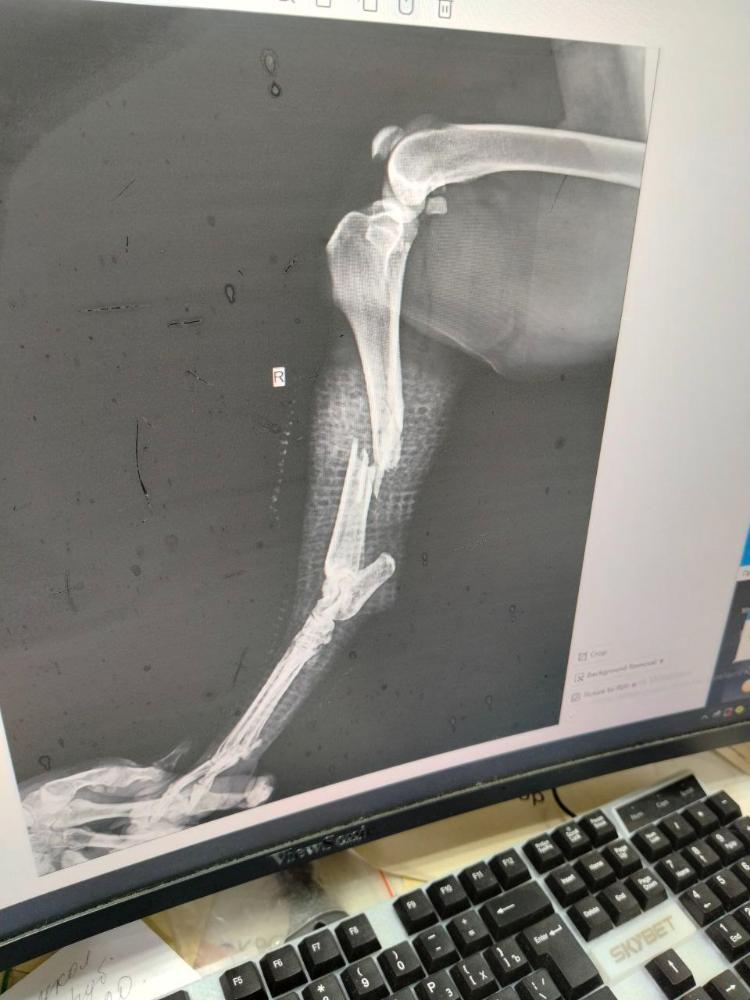

Фаби и Варя Опубликовано 14 декабря Автор Опубликовано 14 декабря (изменено) Всем здравствуйте. Какие новости у нас, Дмитрий Андреевич посмотрел Нору ( так решили её назвать), готов взять её сегодня после 18ч на операцию, кардиолог дал добро на операцию, сделали УЗИ брюшной полости всё достаточно не плохо, за исключением, что Нора в течке( как всегда вовремя). После операции Лена @wina заберёт Норочку к себе. Анализы + кардиолог+ УЗИ+ ренген оплачен ( жду чеки) На операцию нужно примерно 35000р Друзья и гости форума! Помогите нам пожалуйста, будем признательны любой помощи. СБ 4276 3800 4869 9495 ВТБ 2200 2458 0021 3261 или по номеру телефона 89153578481 Ольга Вячеславовна Т. с пометкой Нора Изменено 14 декабря пользователем Фаби и Варя 6